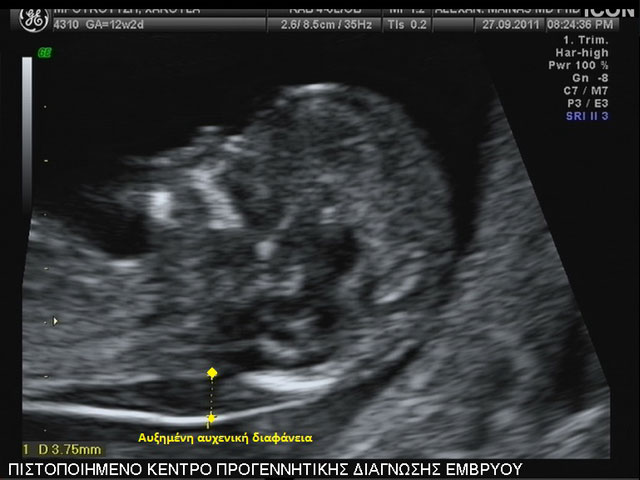

Έλεγχος της αυχενικής διαφάνειας

Το 1866 ο Langdon Down παρατήρησε ότι το δέρμα των ατόμων με τρισωμία 21 ήταν παχύτερο από τα φυσιολογικά άτομα. Το 1992 ο καθηγητής κ. Κ. Νικολαΐδης ανακάλυψε ότι αυτή η πάχυνση μπορεί να παρατηρηθεί υπερηχογραφικά στον 3ο μήνα της κύησης, ως συσσώρευση υγρού στον αυχένα του εμβρύου και ονομάστηκε αυχενική διαφάνεια. Τα τελευταία 20 χρόνια ακολούθησαν εκτεταμένες μελέτες όπου αποδείχθηκε ότι η αυξημένη αυχενική διαφάνεια σχετίζεται άμεσα με χρωμοσωμικές ανωμαλίες, καρδιακές βλάβες και μερικά γενετικά σύνδρομα του εμβρύου. Έτσι πλέον η μέτρηση της εφαρμόζεται σε όλες τις κυήσεις μεταξύ της 11ης και 14ης εβδομάδας σύμφωνα με  ορισμένα στάνταρ, τα οποία διέπουν τη μέτρησή της ώστε το αποτέλεσμα να είναι αξιόπιστο.

Την τελευταία διετία στον παραπάνω συνδυασμό προστέθηκαν και νέοι υπερηχογραφικοί δείκτες πέρα από το γνωστό ρινικό οστό όπως η αυξημένη αντίσταση στη ροή του φλεβώδους πόρου και η ανεπάρκεια της τριγλώχινας βαλβίδας της καρδιάς του εμβρύου. Είναι γνωστό ότι η απουσία του ρινικού οστού ή παθολογική ροή στο φλεβώδη πόρο (αντιστροφή κύματος α) και η ανεπάρκεια στην τριγλώχινα βαλβίδα της καρδιάς παρατηρούνται σε έμβρυα με τρισωμία 21 σε ποσοστά  60, 65, 55% αντίστοιχα, ενώ σε φυσιολογικά έμβρυα σε ποσοστά 2,5, 3 και 1%.

• Μετρηθεί η αυχενική διαφάνεια του εμβρύου